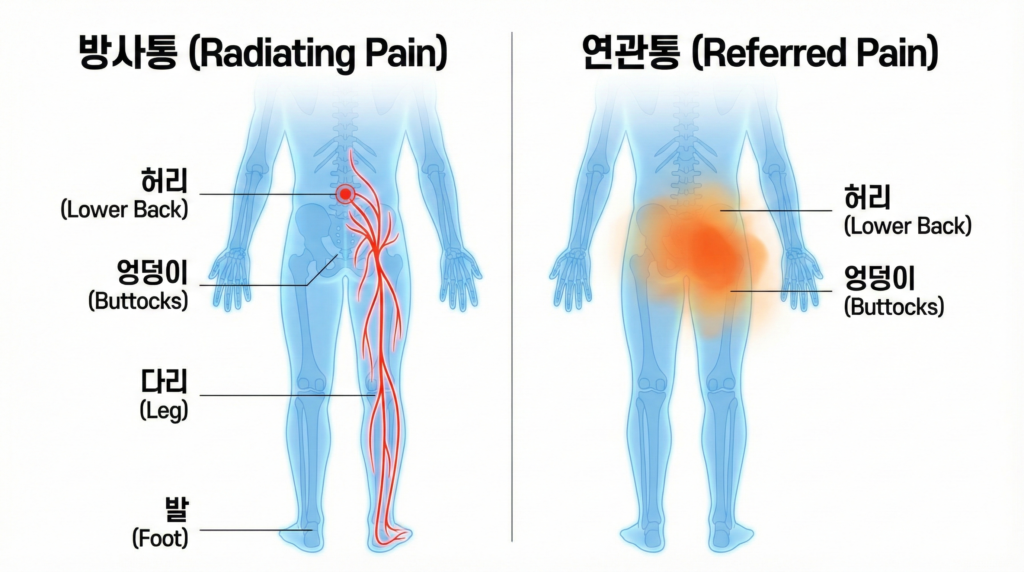

다리가 저린 방사통과 허리만 뻐근한 연관통을 구별하여, 신경주사나 관절 치료 등 내 증상에 꼭 맞는 치료를 받는 것이 중요합니다.

1. 통증의 모양을 보면 원인이 보입니다

허리가 아플 때 가장 먼저 확인해야 할 것은

‘통증이 어디까지 내려가는가’입니다.

전문의들은 이를 통해 통증의 원인을 크게 두 가지로 구분합니다.

1) 방사통(Radiating Pain): “다리에 전기가 오는 것처럼 찌릿해요”

- 특징: 허리에서 시작된 통증이 엉덩이를 지나 허벅지 뒤쪽, 종아리, 심지어 발가락까지 찌릿하고 날카롭게 뻗어 나가는 느낌입니다.

전기가 통하는 것 같거나 화끈거린다고 표현하기도 합니다. - 의심 원인: 이는 십중팔구 신경 문제입니다. 허리디스크(추간판탈출증)나 척추관협착증으로 인해 다리로 내려가는 신경이 눌렸을 때 나타나는 전형적인 증상입니다.

2) 연관통(Referred Pain): “허리랑 엉덩이 주변이 묵직하고 쑤셔요”

- 특징: 통증이 허리나 엉덩이 주변에 국한되어 나타납니다. 뻐근하고, 묵직하고, 쑤시는 느낌이 강합니다.

중요한 점은 통증이 무릎 아래로는 잘 내려가지 않는다는 것입니다. - 의심 원인: 이는 신경보다는 척추 후관절의 염증이나 주변 근육의 문제일 가능성이 높습니다.

“무릎을 기준으로 생각하세요!”

통증이 무릎을 넘어 발목, 발가락까지 찌릿하게 내려간다면 신경 치료가 필요할 가능성이 높고, 무릎 위쪽인 허리와 엉덩이에만 통증이 머문다면 관절이나 근육 치료가 우선일 수 있습니다.